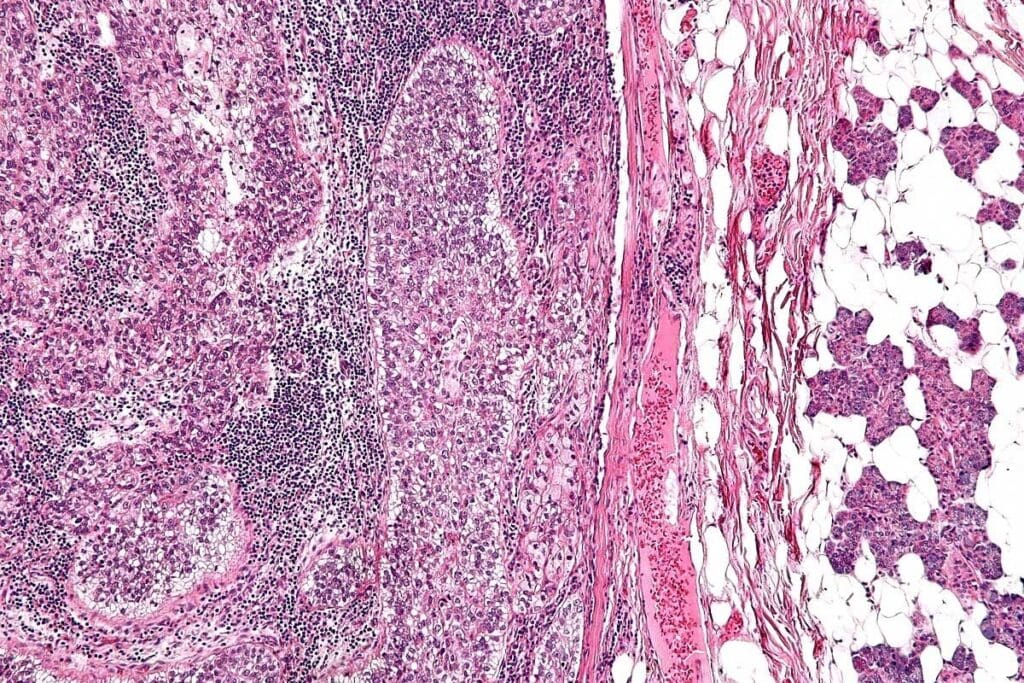

ARMS has specific genetic changes, like the PAX3/7-FOXO1 fusion. These changes are important for diagnosis and treatment. The cells in ARMS are small and round, sometimes forming structures that look like alveoli.

How Alveolar RMS Differs from Other Cancers

ARMS is different from other rhabdomyosarcomas, like embryonal RMS, in its genetics and look. ARMS is more aggressive and often has a worse outlook than embryonal RMS. The unique genetic fusions and histology of ARMS set it apart from other soft tissue cancers.